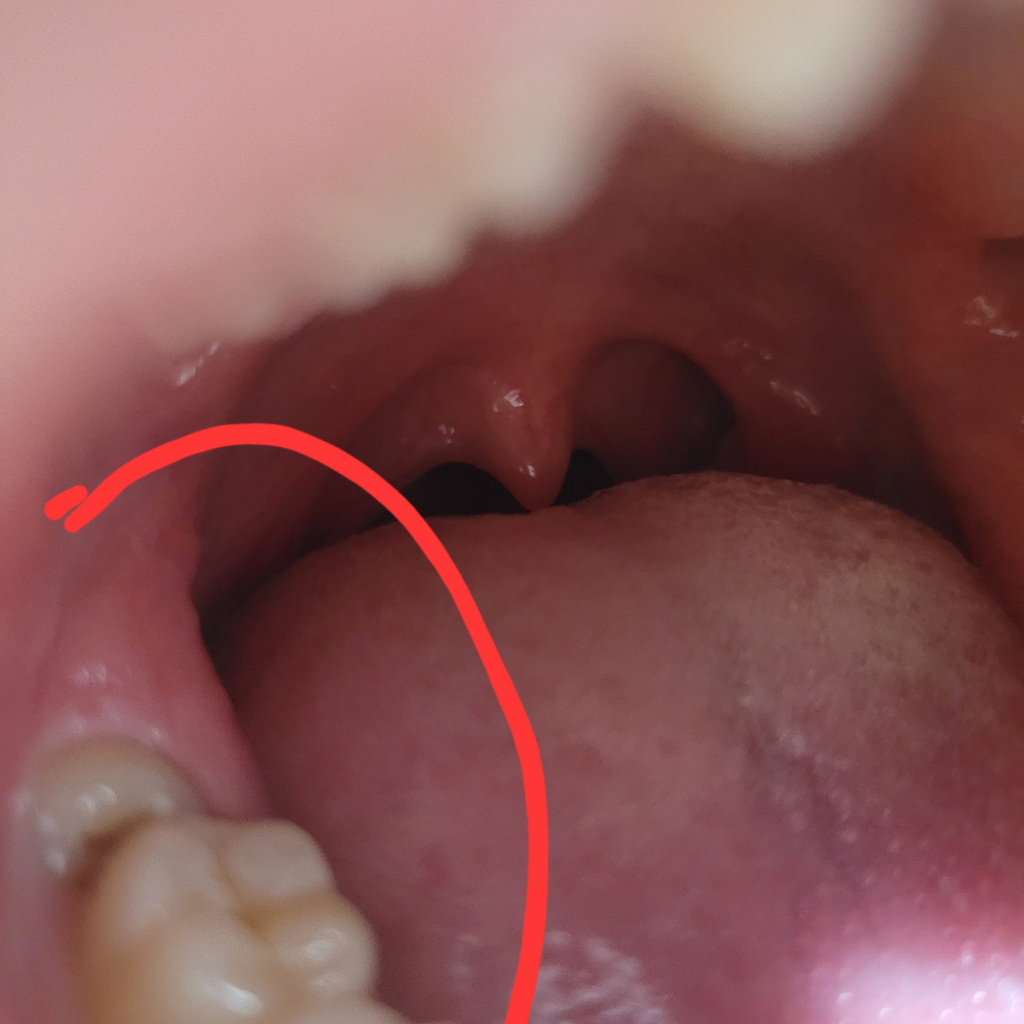

사랑니가 아픈데 혹시 잇몸에 염증이 난 건가요..?

사랑니쪽이 계속 음식을 씹을때마다 아픈데 혹시 지금 사랑니 쪽 잇몸이 붓거나 염증이 난건가요??? 저 사랑니는 매복이겠죠? ㅠㅠㅠㅠㅠㅠ

사랑니 뒷부분 잇몸이 위쪽치아에 씹혀서 상처가 생긴거 같습니다. 계속 불편하시면 사랑니는 발치를 하시는게 좋을것같습니다. 사진상으로는 부분매복같습니다.

사진상으로 크게 문제가 보이진 않습니다만 불편하면 뽑으시는 게 좋고 지금은 판매복이라고 합니다.

해당부위에 사진상으로 염증이 확인되지 않으며, 사랑니가 매복이 되어있는지 치과에 방문하여 엑스레이촬영을 하고,매복이 되어 있는 경우 발치가 필요로 됩니다.